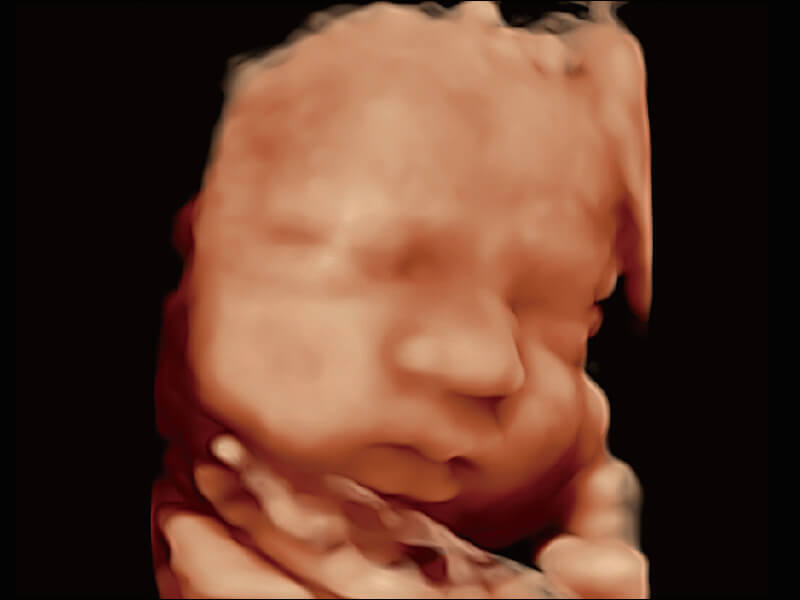

成像功能

超宽频带技术,为容积成像带来优质的二维图像基础,为您呈现丰富的结构细节,栩栩如生地展示宝宝的宫内形态以及各种组织的立体结构。